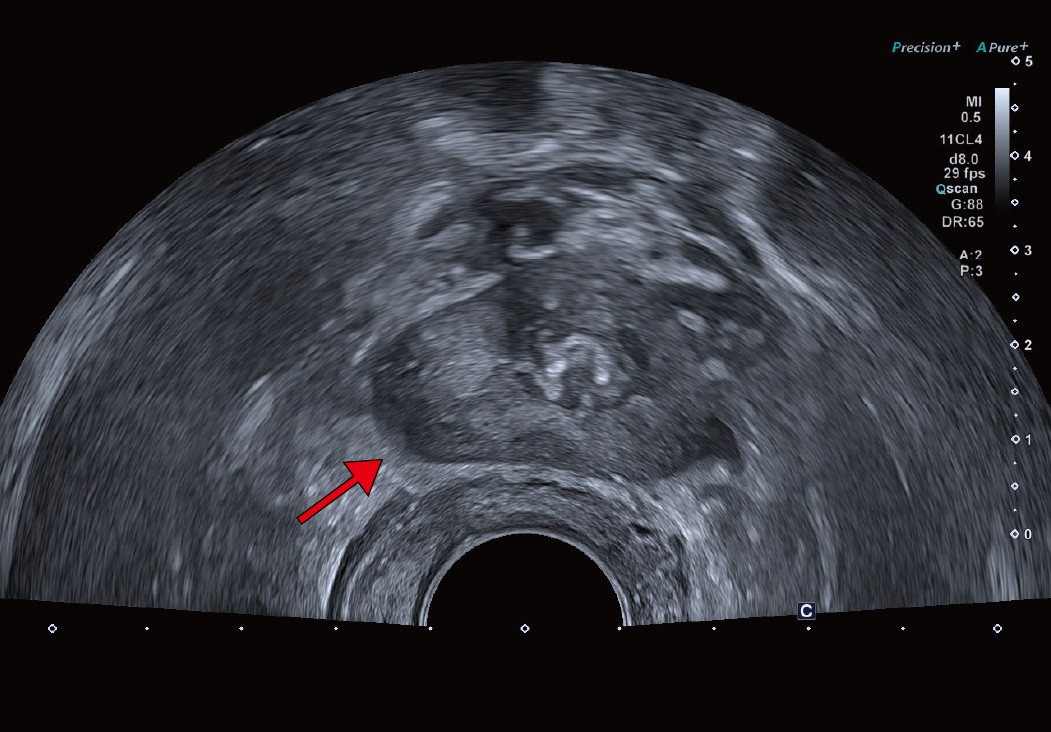

Aplio meによる臨床画像 症例:前立腺がんに対する経直腸エコーによる針生検

a:経直腸超音波画像。前立腺右葉辺縁領域に低エコー領域を認めるが、がんとは断定しづらい。 a:経直腸超音波画像。前立腺右葉辺縁領域に低エコー領域を認めるが、がんとは断定しづらい。

abcd図

クリニックでは、通常の検査のほか前立腺針生検でもSMIを活用している。SMIは、モーションアーチファクトを除去するアルゴリズムを使用し、従来のカラードプラでは描出困難だった微細血管の低流速血流を高感度に描出できる。前立腺針生検は事前にMRI検査を行い、MR画像を参考に会陰部から針を挿入し組織を採取するが、SMIで前立腺がん特有の微細な血流の有無を確認しながら行うため、通常の前立腺針生検より高精度に検査が行える。宮嶋院長は、「MRI所見でPI-RADS(Prostate Imaging Reporting and DataSystem)スコアが4以上であれば、SMIで微小血管血流が検出できる印象です。実際に、SMIによりMRI所見と同様に血流が描出され、腫瘍を検出できた症例もあり、大変有用だと思います」と評価する。